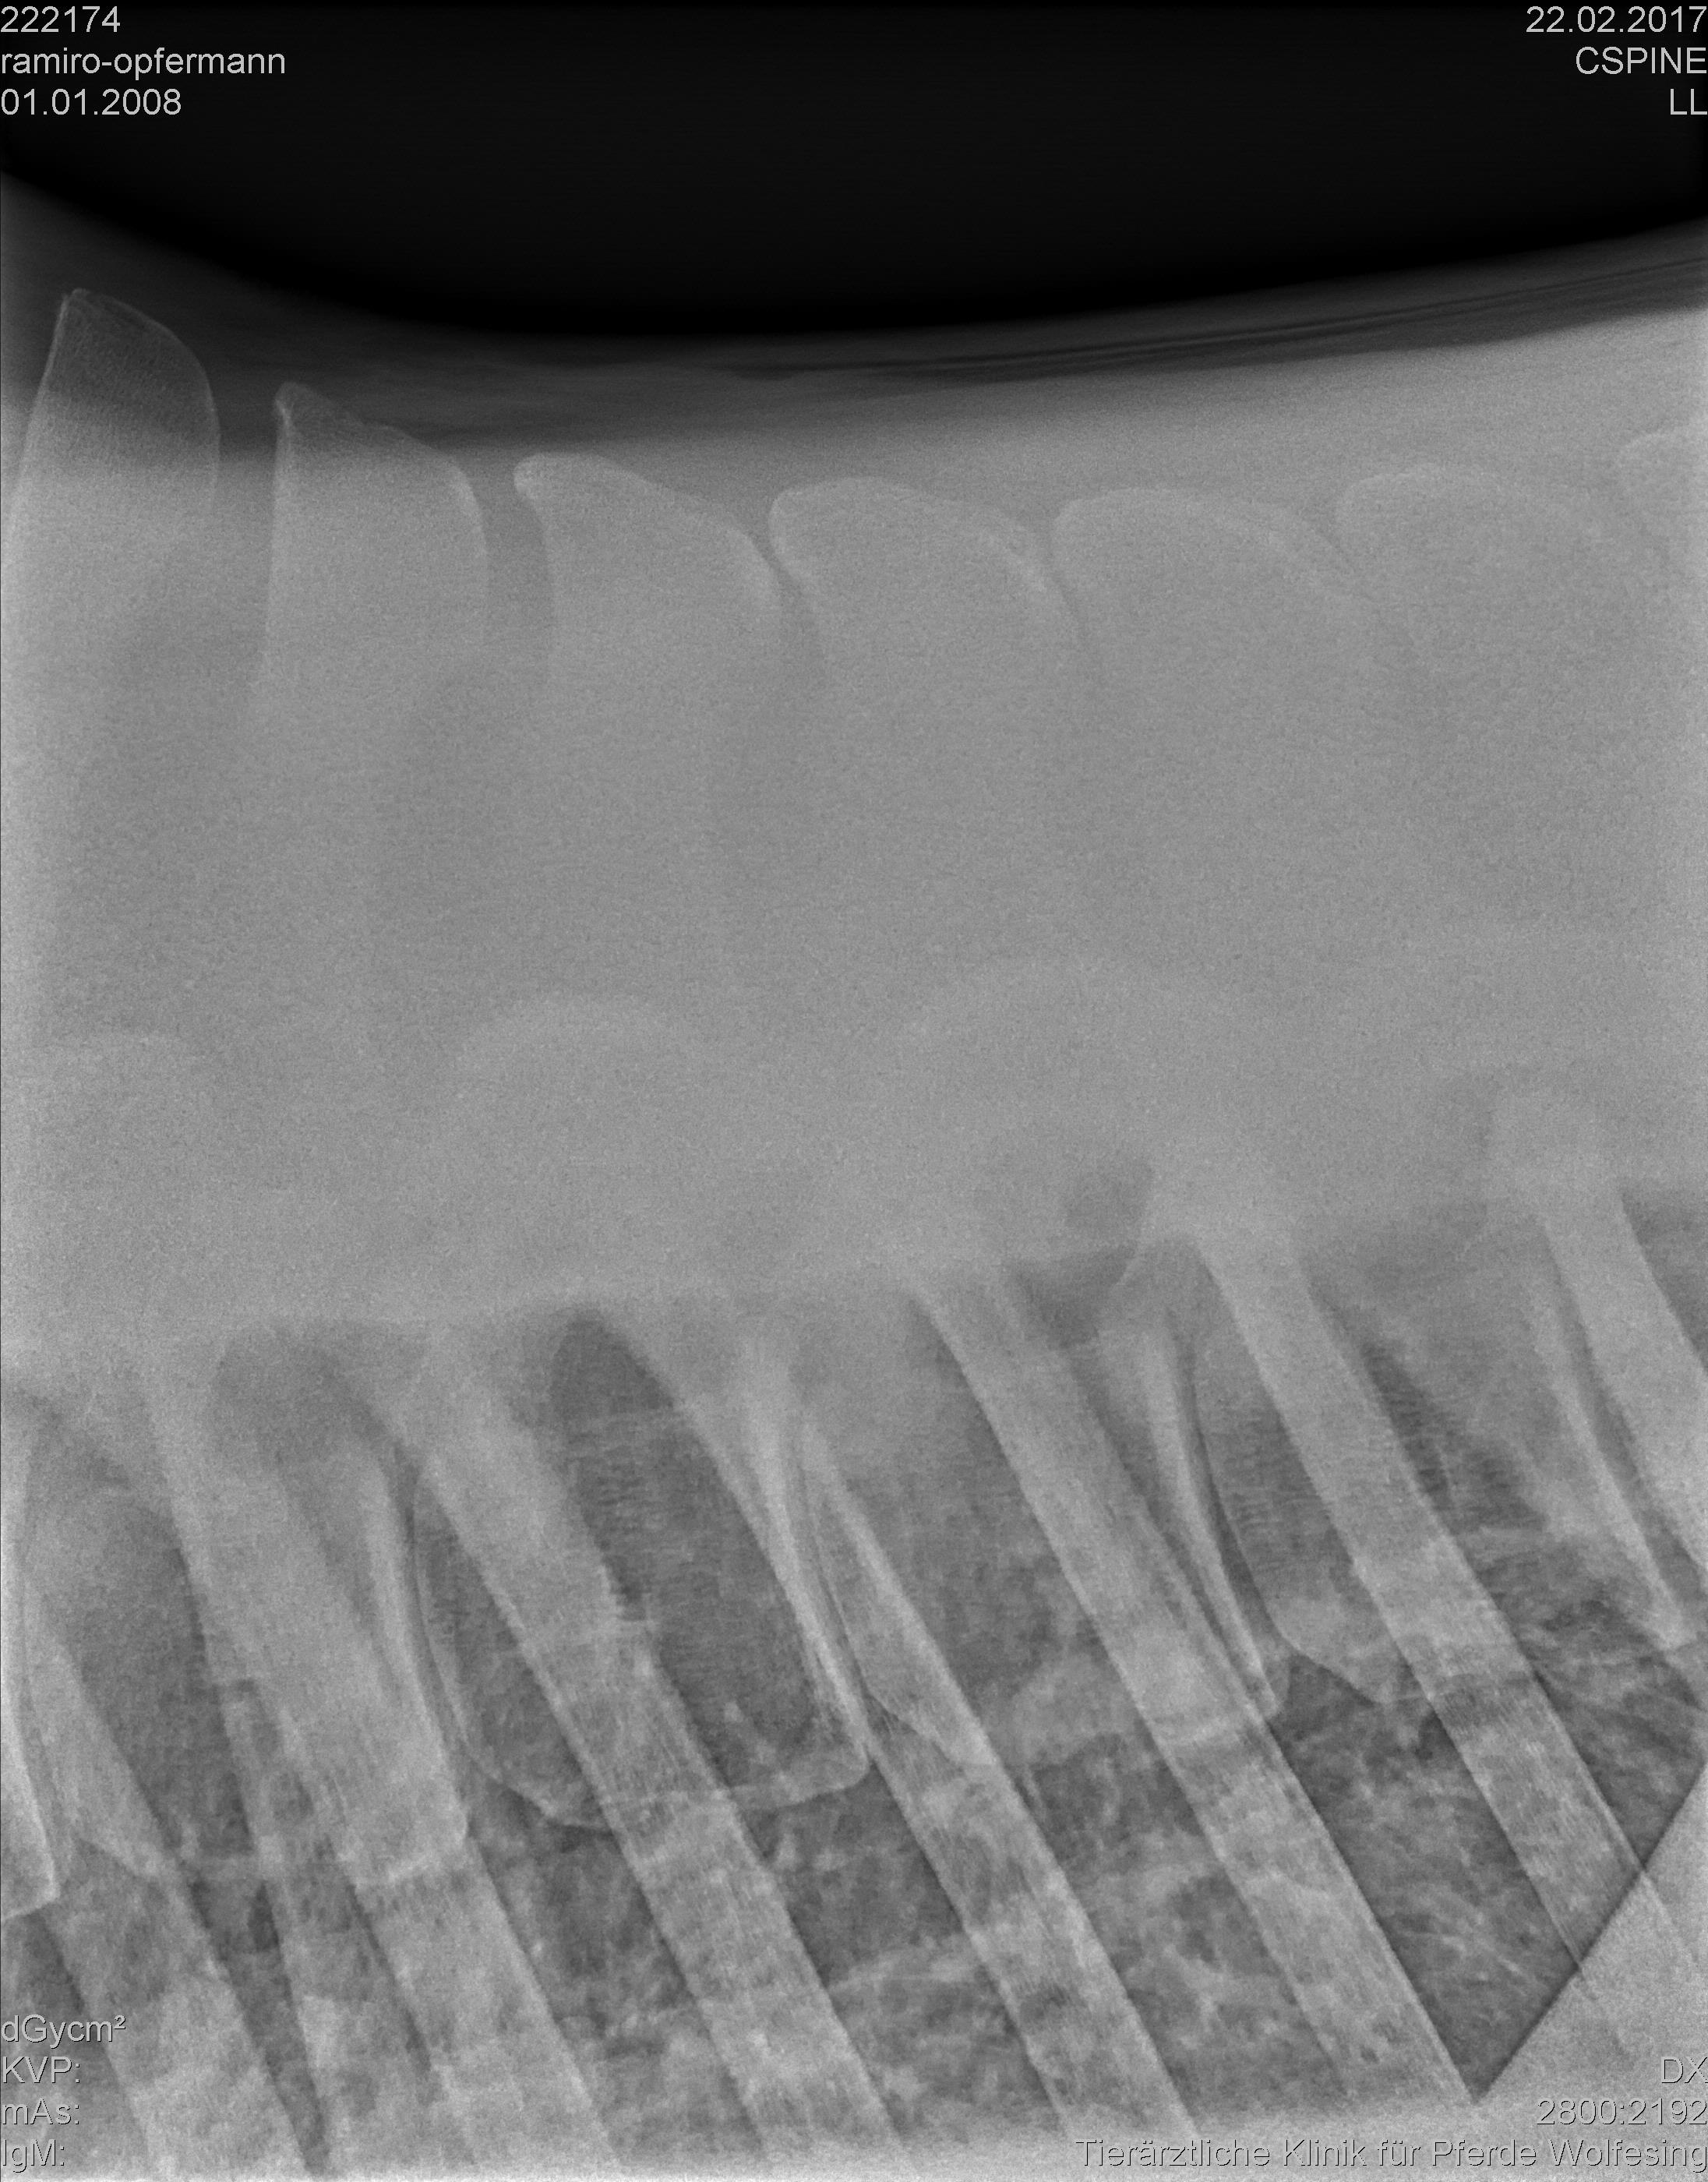

хочу обратиться за помощью, советом и также, возможно, обменяться опытом с владельцами лошадей с подобным диагнозом. А именно – у моей лошади диагноз Kissing Spines.

К моменту постановки диагноза лошадь находилась в моем владении только 3 недели (дата покупки 29.01.2017, дата постановки диагноза – 22.02.2017), т.е. я купила ее уже с этим диагнозом, не зная этого. Рентгены приложила.